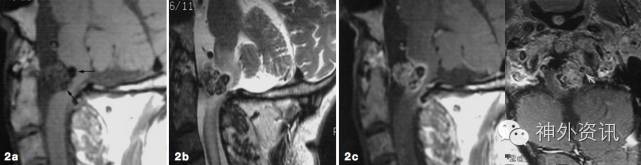

患者1年前无明显诱因下出现左侧手指麻木,中指和无名指为甚,当时无活动障碍,未予重视。后手指麻木症状逐渐加重,伴远端关节活动不利,遂于当地医院就诊,查头颅增强MRI示:右侧额顶部占位,星形胶质细胞瘤首先考虑(图1)。为求进一步治疗转来我院。

图1. 右侧额顶叶内见不规则囊实性占位,前内方为囊样信号影,边界清楚无强化,后外方可见一不均匀结节,T2WI混杂低信号,不均匀强化,周围可见水肿带。脑室、脑池和脑沟形态及位置无殊。中线结构未见移位。